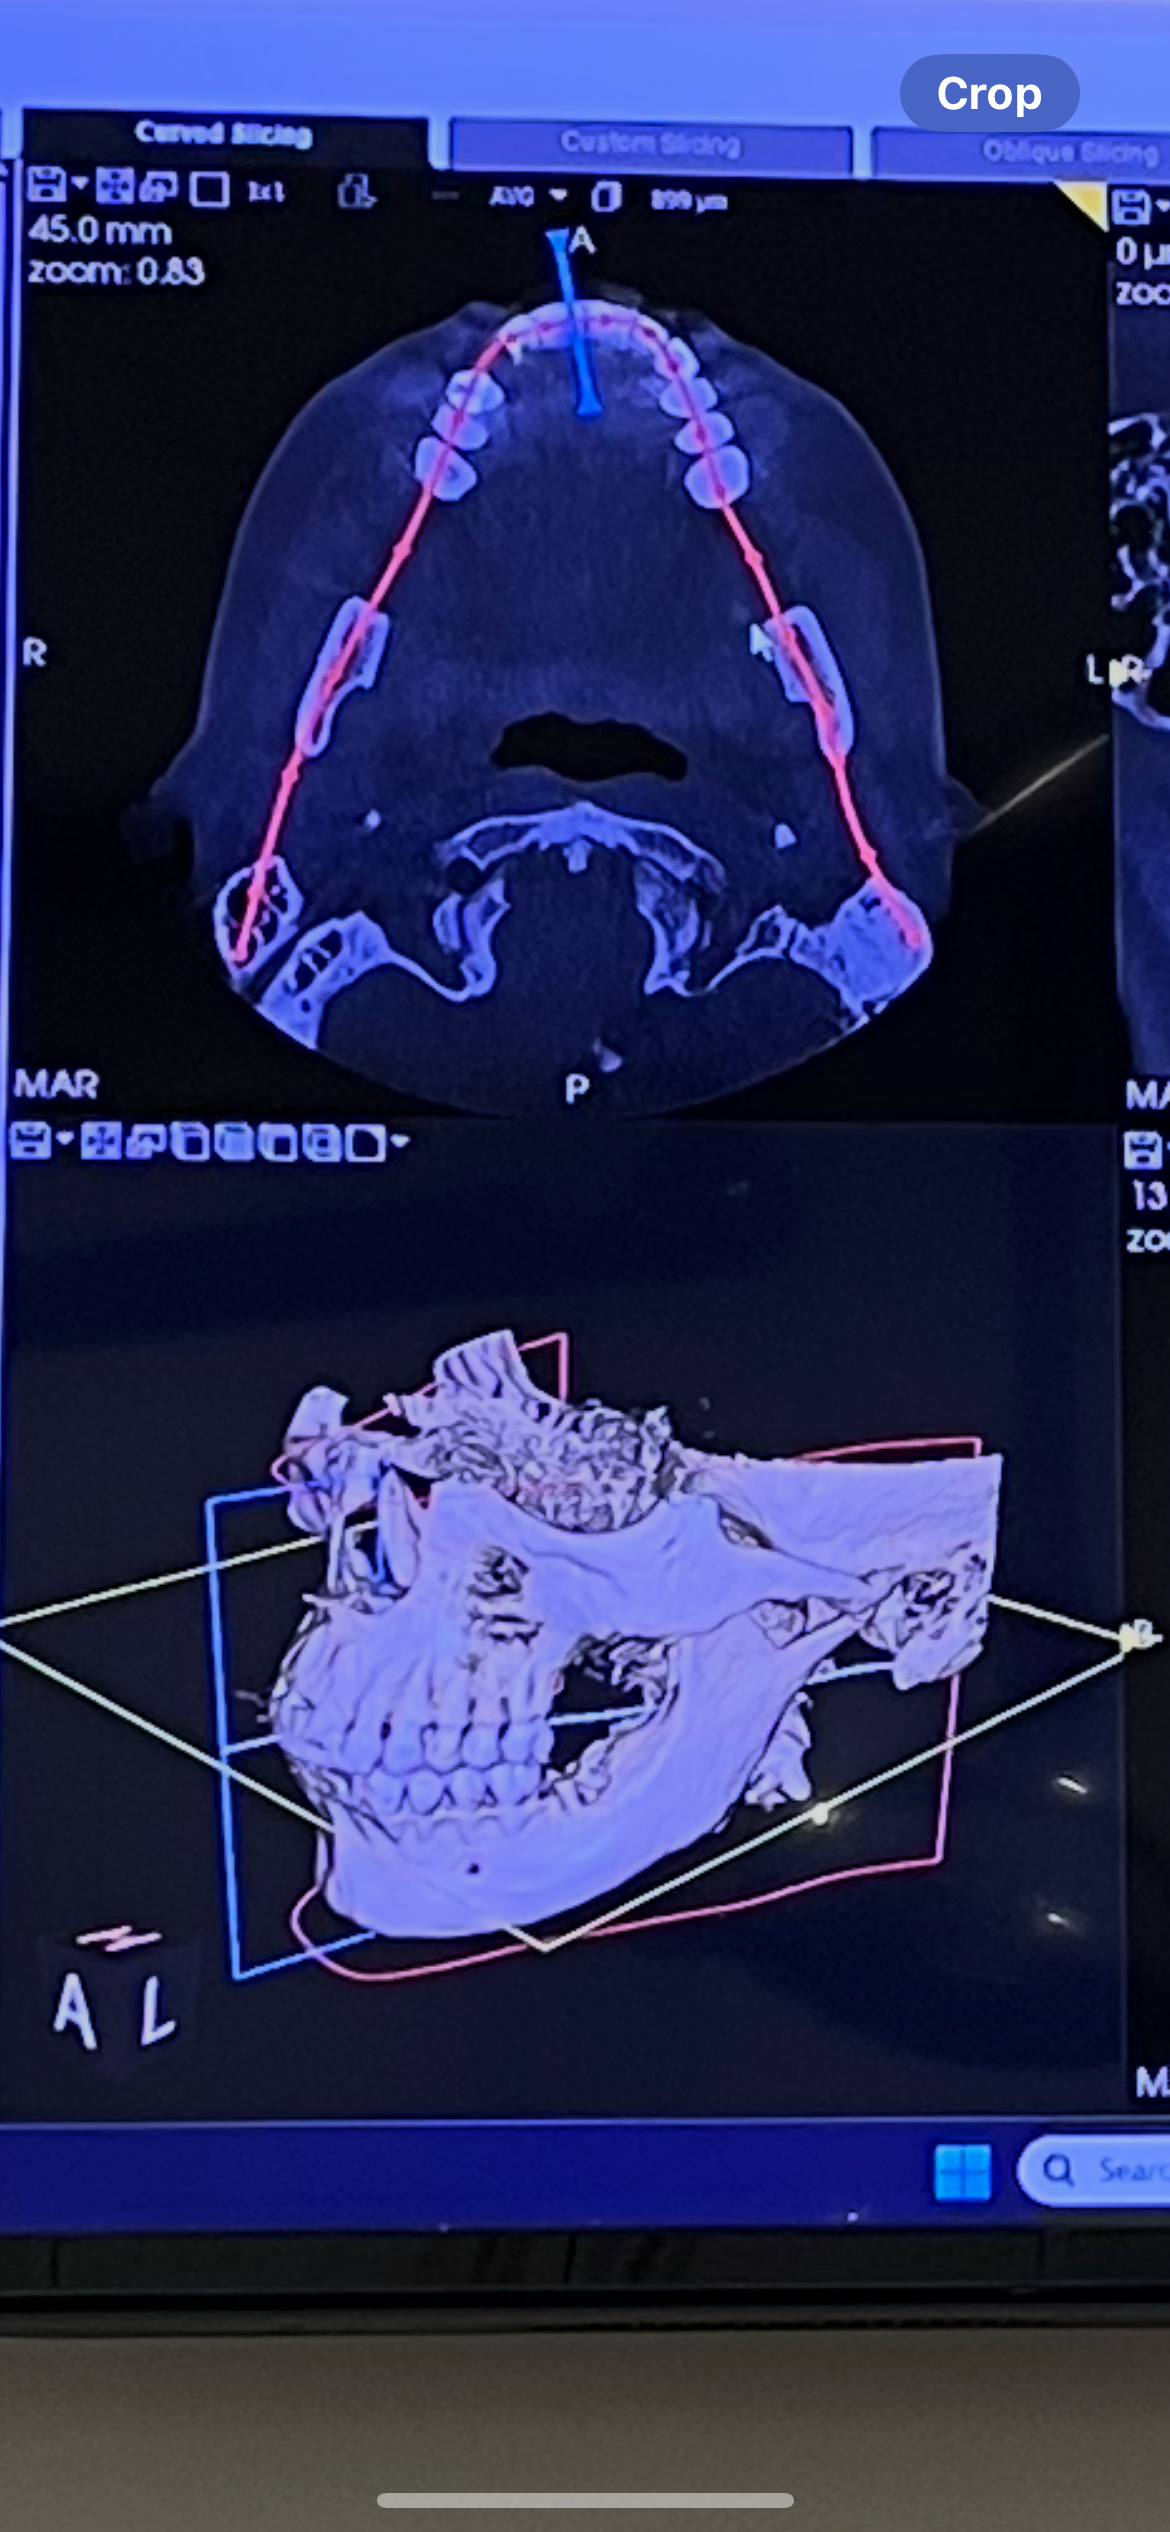

Hello. I’m a windowed, single working mom looking for some financial help on a journey to correct my deteriorating jaw. I broke my jaw in a car wreak as a teen and it’s never been ok since. I need complete joint replacement for both sides, which requires 3-4 months just to make the custom joints. I also need braces to correct my deep overbite. The surgery is costly as everything on this journey is but I’ve put it off far too long. I’m now on soft foods/liquid diet as I cannot chew anymore. Any help you can provide will be greatly appreciated. Even with insurance, this is going to cost a lot of money out of pocket.